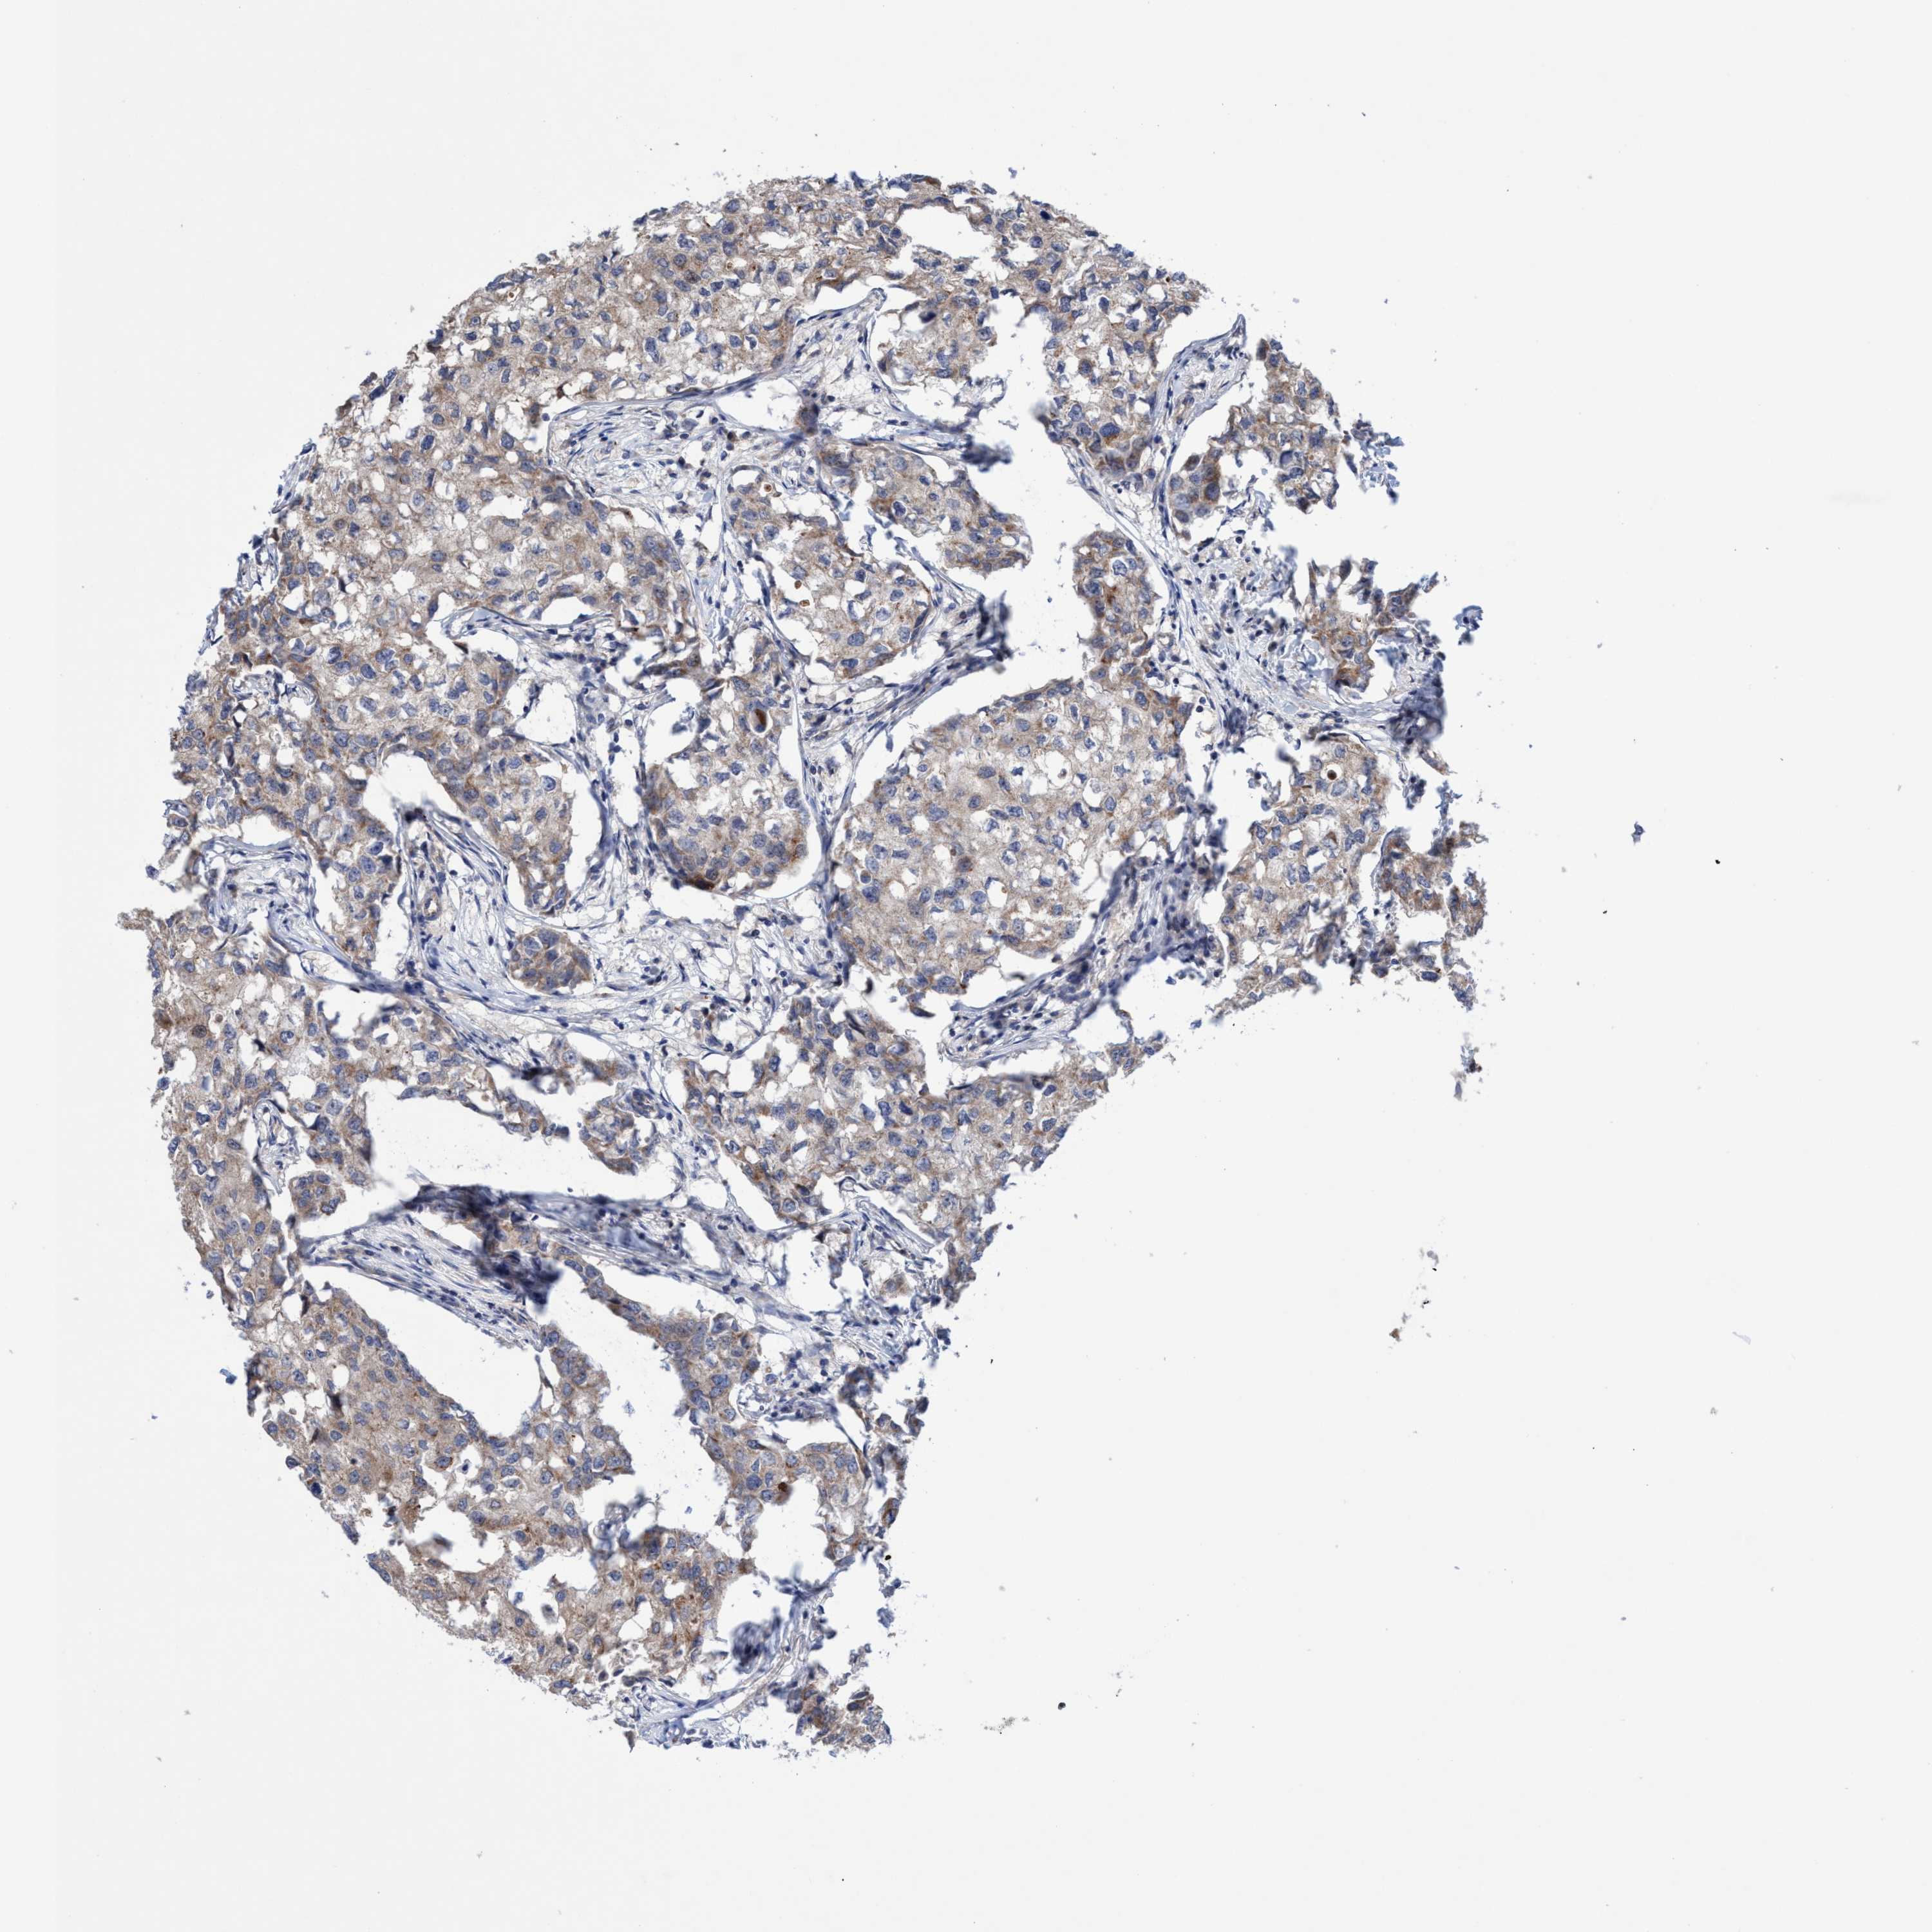

BRCA TCGA BRCA VALIDATION PROTEIN EXPRESSION

ANTIBODIES

AND

VALIDATION